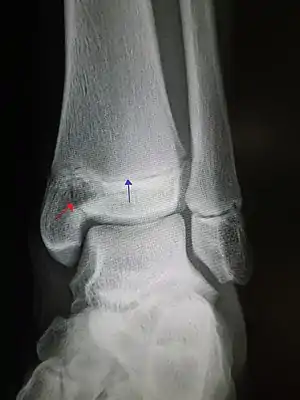

![]() | |

| An X-ray of the left ankle showing a Salter–Harris type III fracture of medial malleolus. Red arrow demonstrates fracture line while the blue arrow marks the growth plate. | |